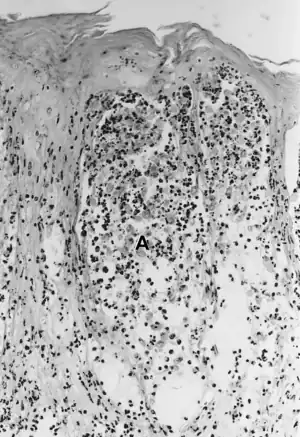

| Foot-and-mouth disease - acantholysis in a sample of a skin vesicle: Necrosis of the stratum spinosum can be observed, and keratinocytes floating in the vesicular fluid (spongiosa). | |

Biopsy section from trunk showing suprabasal acantholysis